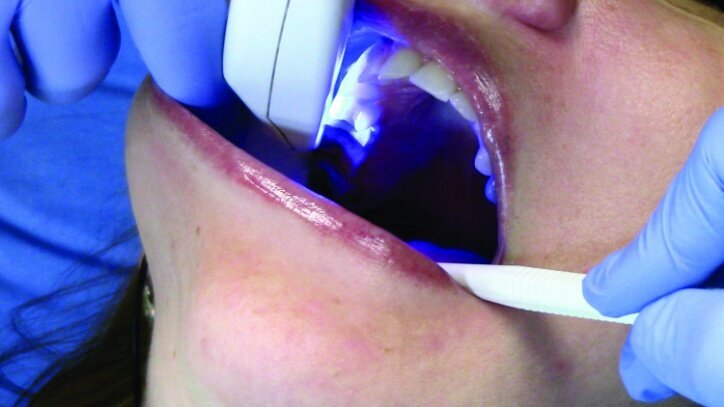

An OptraStick Application Aid (Ivoclar Vivadent) was used to seat the restorations on the teeth because onlays and partial crowns can be difficult to handle. Initial tack curing was completed using a Bluephase curing light (Ivoclar Vivadent) for three seconds at each interproximal area. The resin was then removed easily using a 36/37 scaler from Brasseler. Liquid Strip (Ivoclar Vivadent), a glycerine gel that prevents an oxygen-inhibited layer of the resin cement, was applied to the margins prior to final curing (Figs. 30 & 31).

Final curing of the restorations was then completed (Fig. 32). The initial #00 cords were removed after final curing so proper tissue management could be maintained until curing was completed.